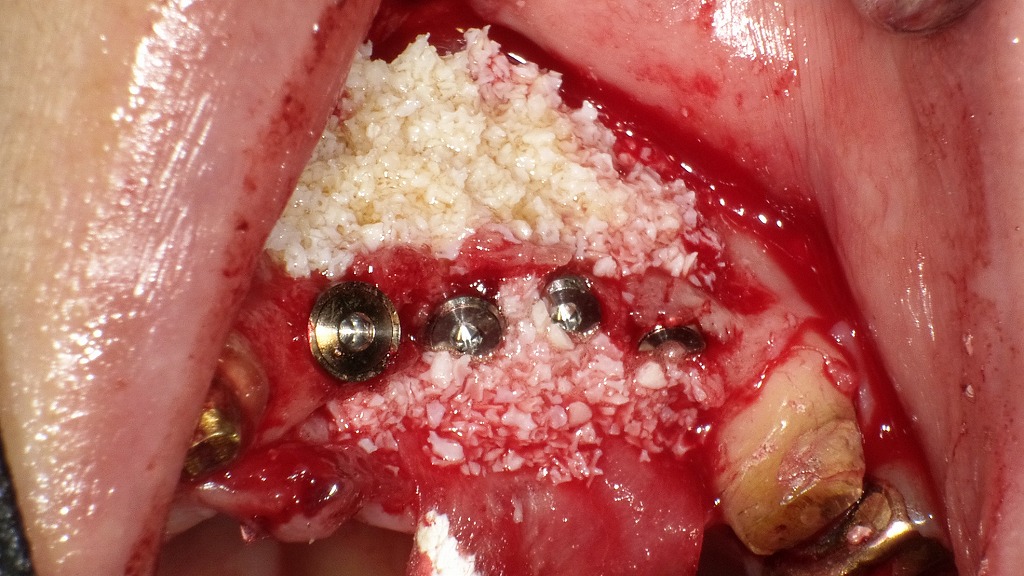

この画像は、左上1番〜4番部位にインプラント埋入と同時に骨造成(GBR)を行った術中写真です。

インプラント埋入と骨造成(GBR) 🦷 手術部位と処置内容

- 埋入部位:左上1番・2番・3番・4番の4本。

インプラント体のヘッド部が確認でき、隣接間距離や歯列弧線に沿って整然と配置されています。 - 骨造成(GBR):インプラント周囲および唇舌側骨欠損部に、**人工骨(骨補填材)**が充填されています。白色顆粒状の部分が人工骨材です。

- CGF(Concentrated Growth Factor):患者自身の血液から作成したフィブリン膜が併用され、人工骨を安定させつつ治癒促進を目的としています。

💡 手術の目的

左上前歯部は骨吸収が進行しており、唇舌側骨が薄く欠損していたため、審美性と長期安定性を確保するための骨造成が必要でした。

インプラント埋入と同時に人工骨+CGFによる同時GBR法を行うことで、- インプラントの初期固定を維持

- 骨量不足部の再生

- 軟組織の早期治癒促進

が期待されます。

🔍 術後の流れ

- この後、メンブレン(吸収性膜)で覆い、粘膜を縫合閉鎖して治癒を待ちます。

- 約4〜6か月の治癒期間を経て、骨成熟後に**アバットメント装着・補綴(ブリッジまたは連結冠)**へと移行します。